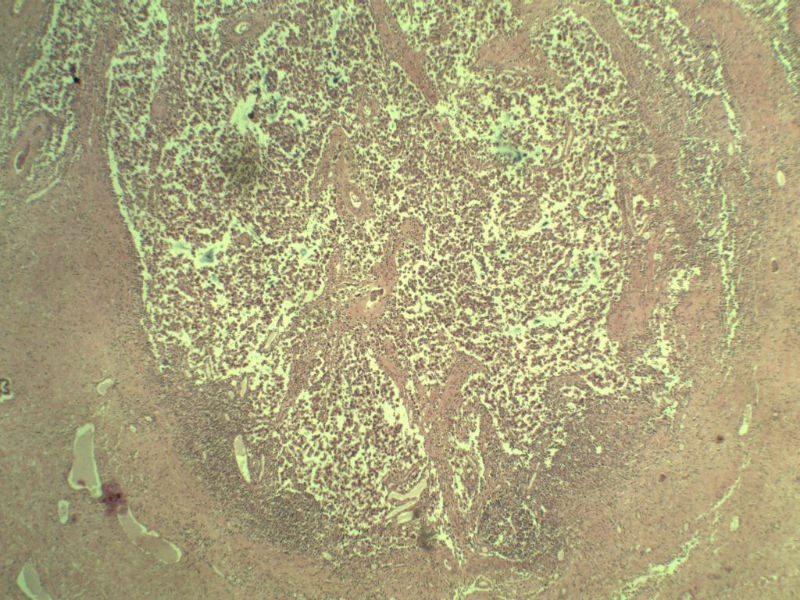

男 27岁 腹腔隐睾 5*3*2 cm, 切面灰红灰黄、实性、质中,请各位老师看看,是精原细胞瘤吗?感觉不像.腹腔隐睾图1

精原细胞瘤

典型的精原细胞瘤,隐睾易恶变